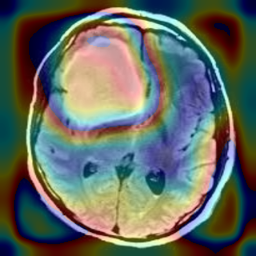

Figure 1: Heatmap Comparison of Unhealthy Images. Different columns show unhealthy MRI images of different positions, sizes, and textures. The first row is the raw image. The second row is the heatmap predicted with PatchCore. The third raw is the heatmap predicted with the proposed method.